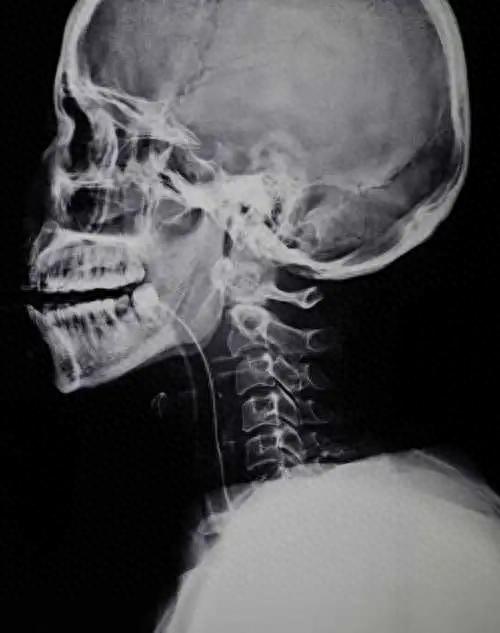

X射线如今常应用于医学影像检查,它可以穿透物体并在荧光屏上显示出影像,帮助医生诊断疾病,比如拍胸片、牙片、骨片等等。

他用这种射线照射了自己妻子的手,并在感光板上留下了手骨和戒指的影像这是人类历史上第一次看到了活体内部的影像。

许多人开始重复和扩展他的实验,探索X射线的性质和应用。X射线最早被应用在医学领域,作为一种无创的诊断工具,能够显示出人体内部的骨骼、器官、肿瘤等情况,对于诊断疾病、定位异物、指导手术等有着巨大的价值。